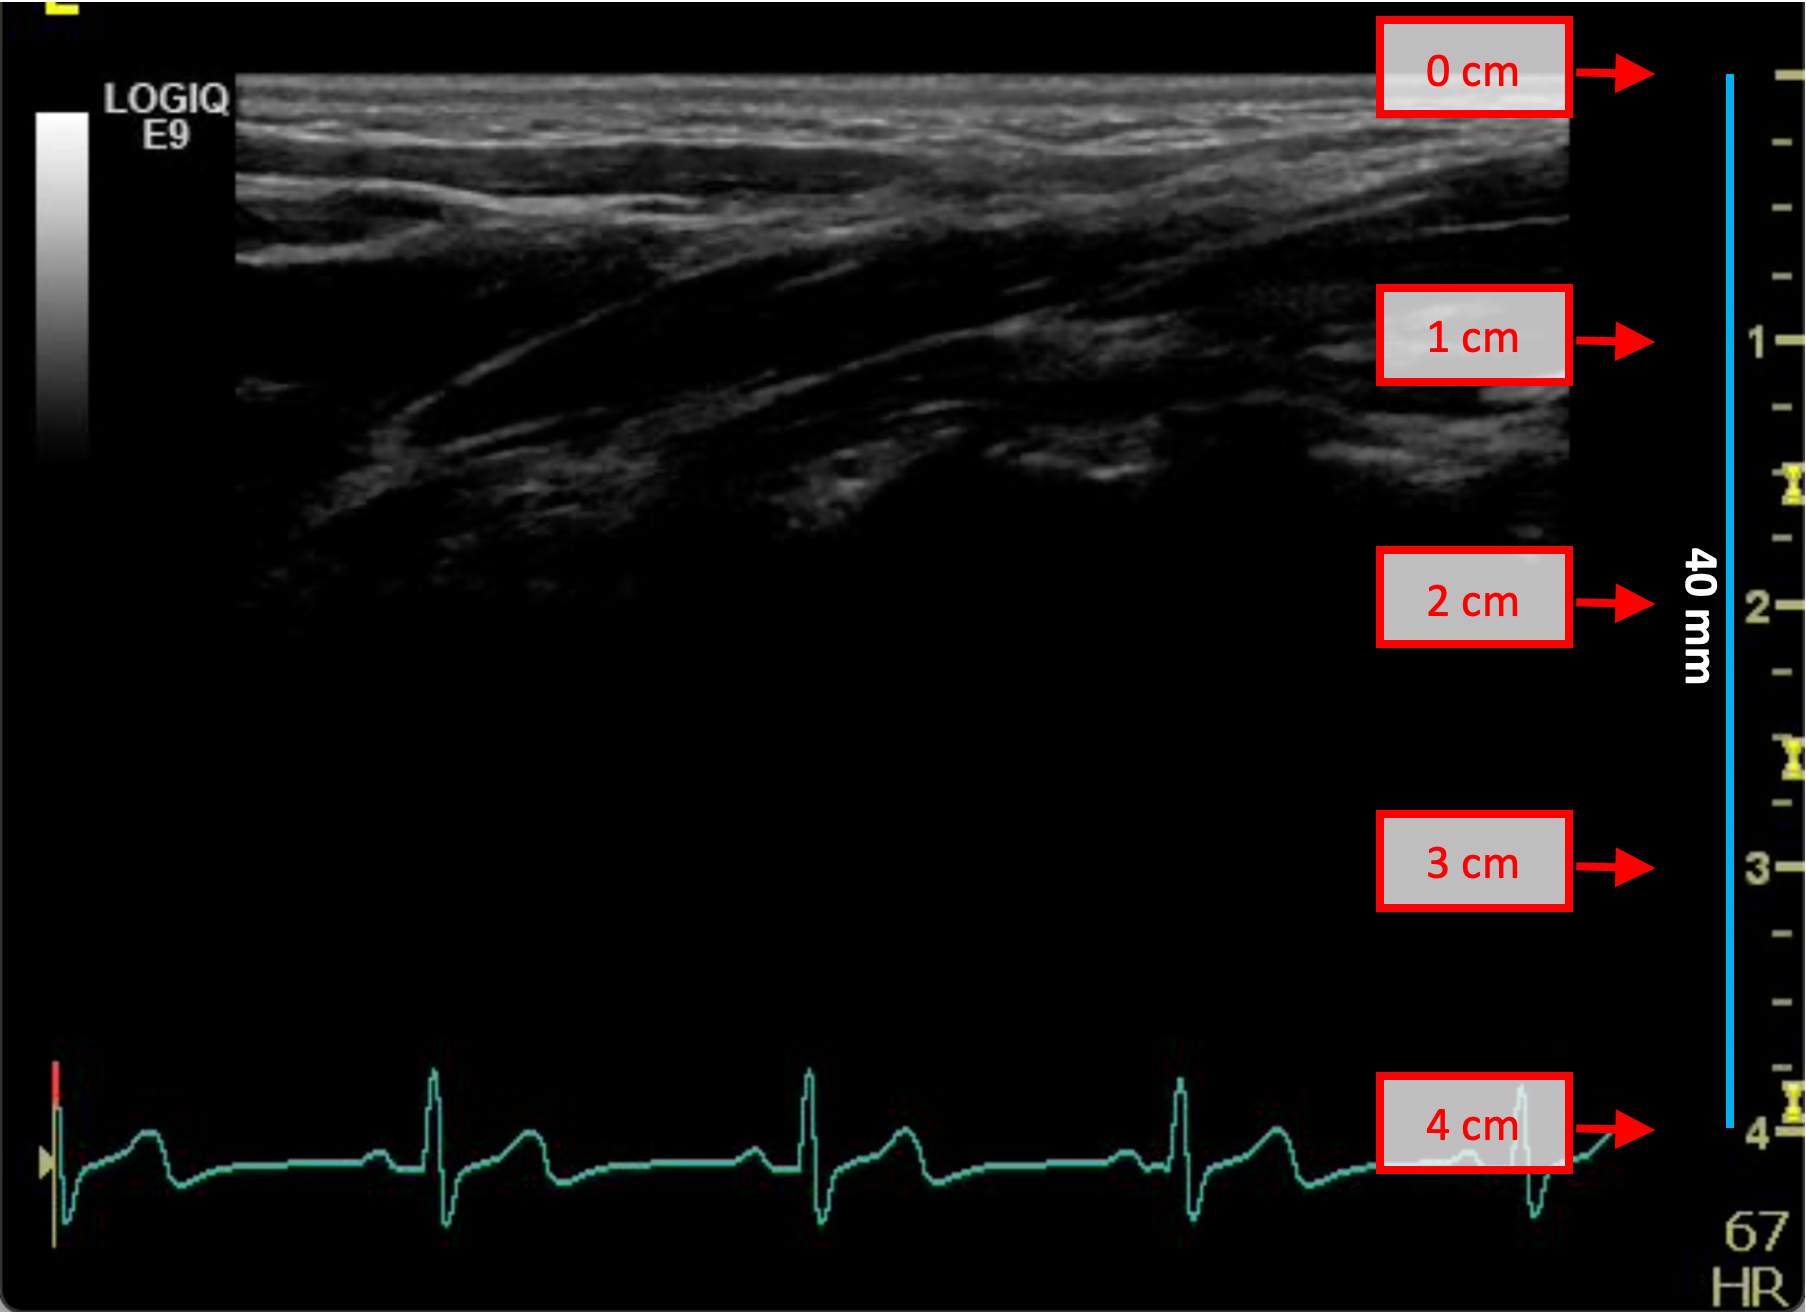

Exemples d'étalonnage en mode B

Les images suivantes présentent des exemples d'étalonnage de l'image en mode B. Les éléments graphiques en rouge indiquent où trouver les informations relatives à la profondeur de l'image échographique.